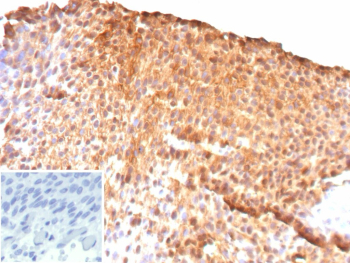

Immunohistochemistry analysis of UPK2 antibody in human bladder carcinoma. Formalin-fixed, paraffin-embedded human bladder cancer tissue was stained with Uroplakin II recombinant rabbit monoclonal antibody (clone UPK2/13669R). Strong HRP-DAB brown membranous and cytoplasmic staining is observed in tumor epithelial cells, consistent with Uroplakin 2 expression in urothelial-derived carcinoma. The staining highlights cell membranes and apical surfaces with diffuse cytoplasmic signal in positive tumor cells, while adjacent stromal elements show minimal background staining. Inset: PBS was used in place of the primary antibody as a negative control. Heat-induced epitope retrieval was performed in 10mM Tris with 1mM EDTA, pH 9.0, for 45 min at 95oC followed by cooling at room temperature for 20 minutes.